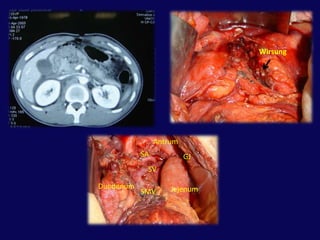

WirsungAntrumSAGJSVDuodenumJejenumSMV

38

HepatoduodenalligamanPankreasDuodenum 2. kıta

PortalvenSMV

Portal venKoledokSplenik venDudenumSMVPankreas başı